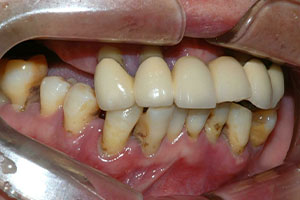

치료증례 전후사진

Before & After